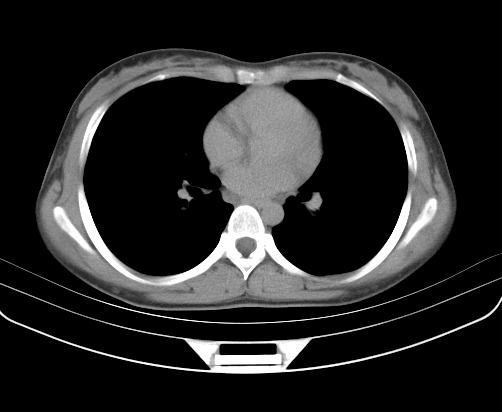

动脉期